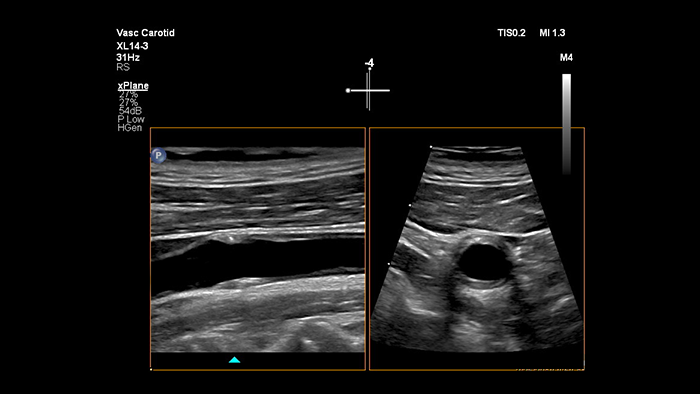

O transdutor XL14-3 xMATRIX fornece imagens xPlane que vão além da abordagem convencional aos exames vasculares ao oferecer imagens em tempo real nos planos tanto longitudinal como transversal simultaneamente. O principal benefício: as imagens xPlane eliminam a necessidade de rodar o transdutor para adquirir vistas ortogonais. Um simples movimento do trackball pode proporcionar uma avaliação anatómica completa, poupando tempo de exame.